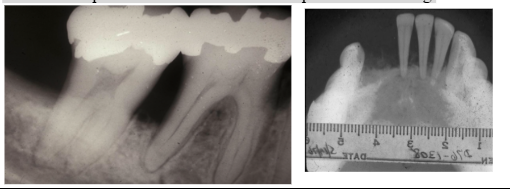

*Reduced trabecular pattern

*Enlarged marrow spaces

*“Hair-on-end” on skull x-ray

*”Hair-on-end” appearance on skull xray

*Enlargement of liver & spleen, lymphadenopathy

*Enlargement of maxilla and mandible (“chipmunk faces”)

*Altered trabecular pattern

*Most common: skeletal pain – due to bone lysis by accumulation of tumor cells → multiple punched out radiolucencies with ill-defined margins/lack sclerotic border → pathological fractures

*Jaw lesions → pain, swelling, numbness, tooth mobility

1. Single/multiple punched out lesions of skull and/or jaws

*Radiograph: irregular radiolucent areas

- can mimic periodontal disease or periapical cysts/granulomas